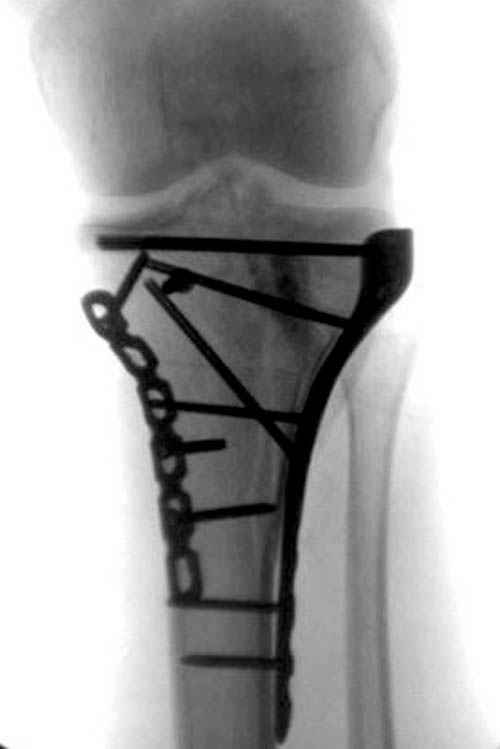

Уважаемые коллеги! В прошлую пятницу больной прооперирован - как и планировалось мыщелковая LCP от ChM. Малоинвазивно не получилось - один большой доступ :(. (но с минимальным скелетированием б/б кости). Наружный мыщелок собрали, но по контролю видно, что задне-медиальный отдел метаэпифиза смещен. Фиксировать не стали (?). 4-е сутки после операции - по м/тканям без проблем. Дополнительная иммобилизация синтетическим тутором.

P. S. перелом диафиза на контроле не совсем захвачен, но проблем там нет. Приношу извинения за низкое качество Р-грамм - выполнены на сканере (фотоаппарат не работает :)) .

Трудно поверить, что разрекламированная Ортопедическая школа Восточной Украины позволяет такие странные снимки? На прямом снимке сохранен общий контур плато, но не известна судьба импрессии суставной поверхности. На полубоковой?, оставлен без репозиции задне-медиальный отдел, и навряд ли после такой фиксации можно удовлетвориться результатом.

Такая ситуация характерна для многих, когда принимается ошибочное решение, т.е пытаются фиксировать одним имплантом переломы двух мыщелков. Латеральная пластина приемлема только для тех случаев, когда сохраняется интактным медиальный диафизарный кортекс и отсутствует фрагментация на верхушке медиального перелома.

При сложных переломах тибиал плато для своего рода Damage Control мы иногда применяем поэтапную тактику. Сперва оперируется одна сторона, а потом после рекондиции мягких тканей окончательный этап.

Если состояние мягких тканей позволяет, я бы предложил такой метод для вашего больного. Без предварительного планирования будет трудно, но шанс не надо упускать. Всего несколько дней после операции, и такая тактика лучше, чем недовольный молодой пациент.

Доступ к медиальной стороне задний или медиальный, через pes или в пространстве между medial gastroc мышцы.

Надеюсь, представленные снимки разных случаев помогут разобраться в тактике, и критика примется без личной обиды.